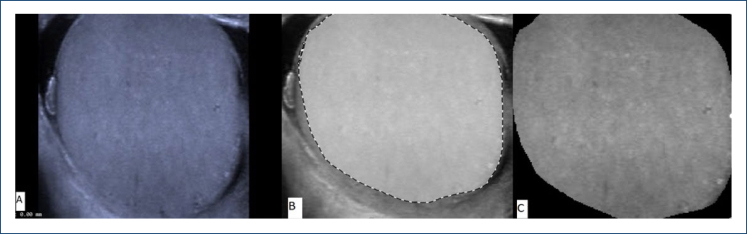

Methods: Ultrasound images of 50 patients who were shown to have COVID-19 infection by polymerase chain reaction method and 50 healthy volunteers who did not have any complaints and were polymerase chain reaction negative were evaluated retrospectively. While forming the patient and control groups, people who smoked or had diseases such as varicocele, which caused testicular parenchyma to be affected, were excluded from the study. Tissue histogram analysis was performed on the images obtained, including the entire testicular parenchyma, and radiomics were obtained. The Mann-Whitney U test and independent samples t-test were used to compare parametric and non-parametric results in independent groups.

Results: The average age of the patient group and control group was 32.13±7.3 years and 31.23±7.9 years, respectively, and no statistically significant difference was detected (p>0.05). When testicular volumes in the patient and control groups were compared, no statistically significant difference was detected (p=0.58). Statistically significant differences were found between the two groups in the radiomics examined using skewness of histogram, zone-size non-uniformity of gray-level size-zone matrix, information measure of correlation of gray-level co-occurrence matrix, run percentage of gray-level run-length matrix, high gray-level run emphasis of gray-level run-length matrix, and kurtosis of histogram (p<0.05). There was no significant difference in other parameters.

Conclusion: Ultrasound histogram analysis may be useful in showing heterogeneity, which is an indicator of the impact on the testicular parenchyma in people with COVID-19 infection. Thus, in addition to other clinical findings and laboratory parameters, ultrasound histogram analysis may be helpful in demonstrating testicular parenchymal involvement in the follow-up of patients after COVID-19.